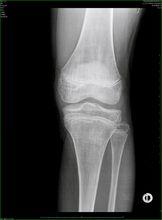

5 GH缺乏的診斷依賴於體格檢查和實驗室檢查.如果證實有GH釋放減少,其他垂體激素的分泌也應該檢查.所有兒童身高體重的增長數據應記錄在生長圖上(發育評價).應拍攝左手X線片(按常規)確定骨齡.GH缺乏時骨齡成熟延遲通常與身高相一致.10%~20%患者的蝶鞍小於正常.用CT或MRI檢查垂體腺或蝶鞍以排除鈣化或腫瘤.

2.3 骨齡遲緩,低於實際年齡4年以上,骨骺融合延遲。蝶鞍大小可無特殊,但鞍區病變者可有鞍上鈣化、蝶鞍擴大,骨質破壞。